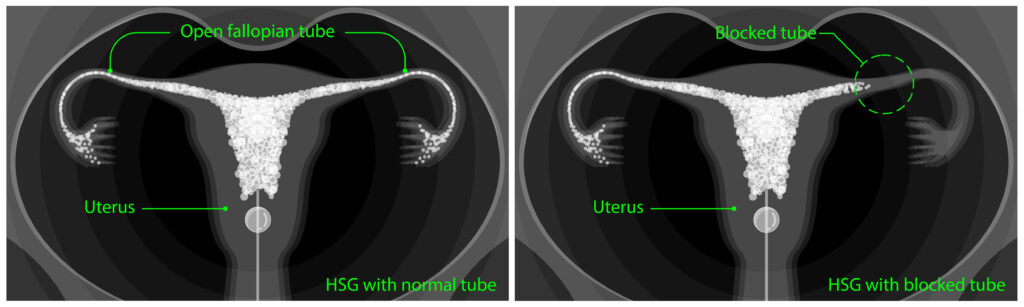

FTR does not require any surgery. It reopens the fallopian tubes. There is no need to make any cuts during FTR. A medical tool, called a speculum, is used to keep the vagina open. Then, the doctor inserts a catheter, a thin plastic tube, into the uterus through the cervix.

Then, a contrast liquid is inserted through the catheter and an X-ray is of the uterus is taken to detect the blockage. Then, the doctor will insert a second catheter to remove the blockage.